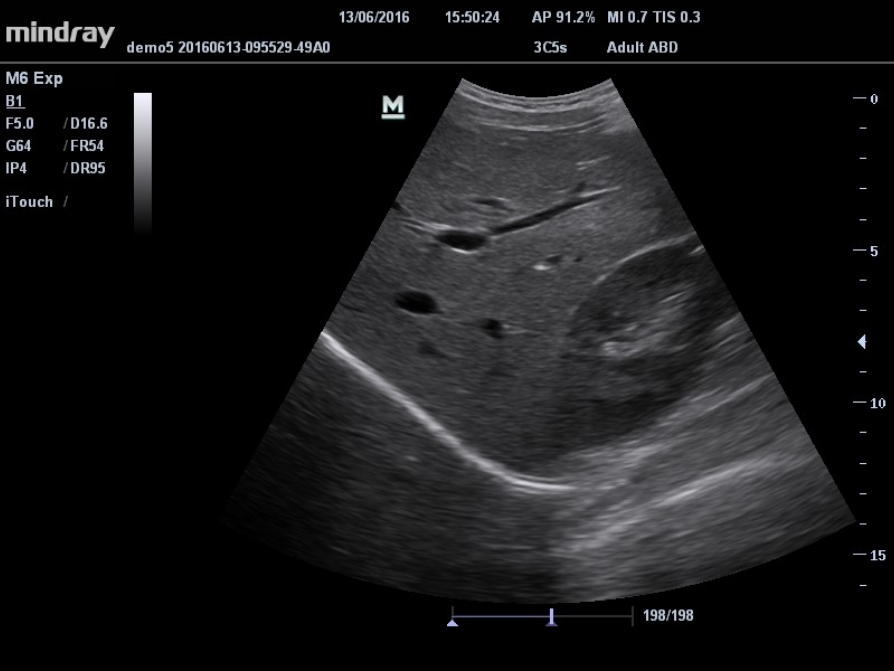

iTouch? (automatyczna optymalizacja obrazu)

Funkcja ta pozwala uzyska? natychmiastow? automatyczn? optymalizacj? obrazu w trybach B, Kolorowego Dopplera i PW (Spektralnego Dopplera Fali Pulsacyjnej) poprzez naci?ni?cie jednego klawisza.